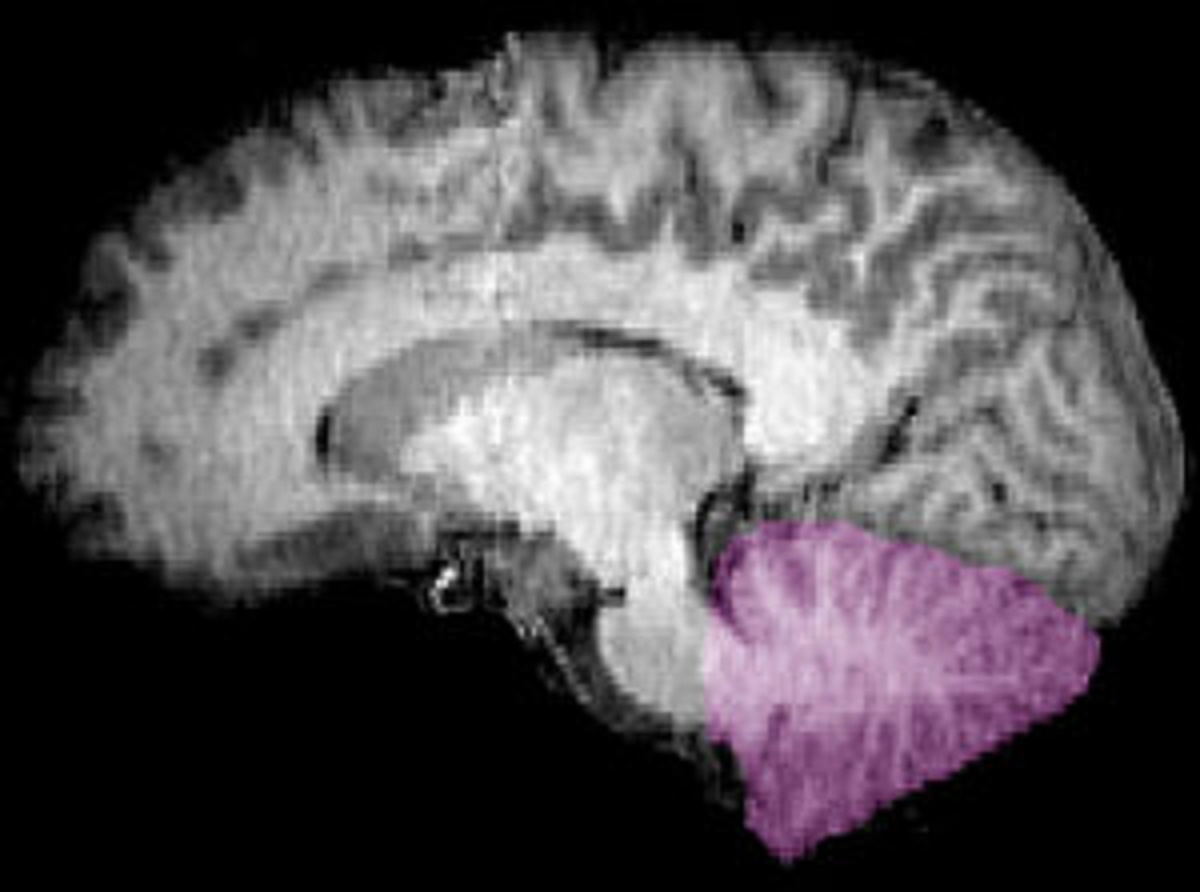

Imagen de resonancia magnética nuclear de una sección sagital de un encéfalo humano. Cerebelo en púrpura. Fuente: Wikipedia.